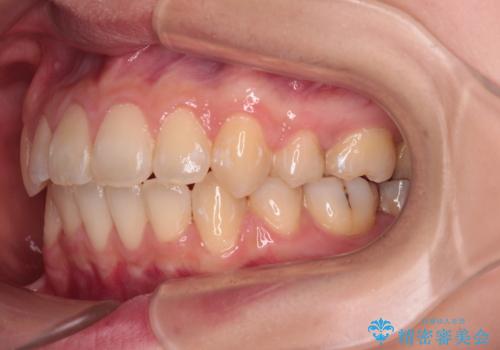

- 前歯のデコボコや口元の突出感、口の閉じにくさを気にして来院された患者様です。

上下左右第一小臼歯4本を抜歯し、ワイヤー装置にてデコボコを解消しながら口元を引っ込めるよう矯正治療を行うこととしました。

抜歯スペースを閉じている過程で、左側の上下犬歯が引っかかってしまい、進捗が停滞しましたが、当初予定の2年~2年半の間で無事に治療を終えることができました。